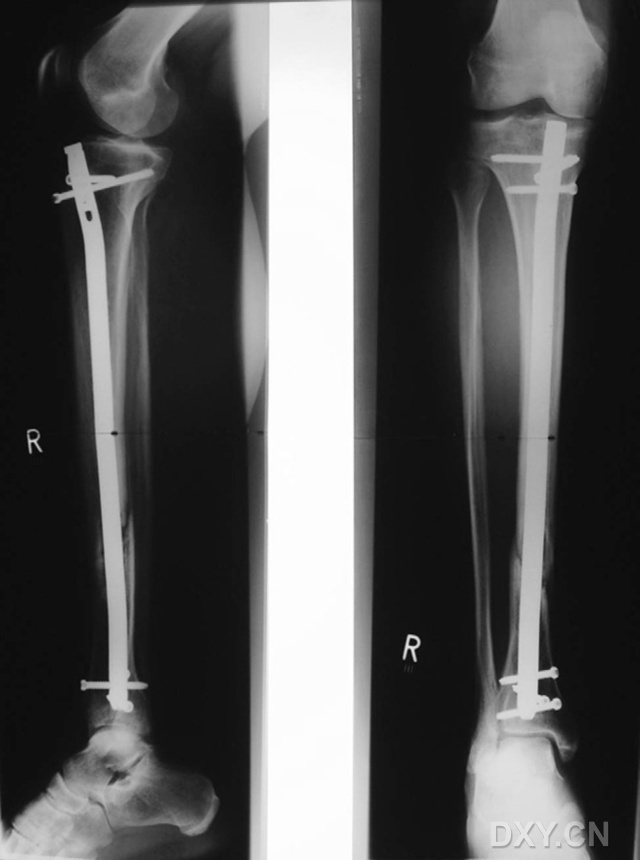

圖1 男性,21歲,從不吸煙,脛腓骨骨折術后9個月,X線片顯示骨折愈合良好。